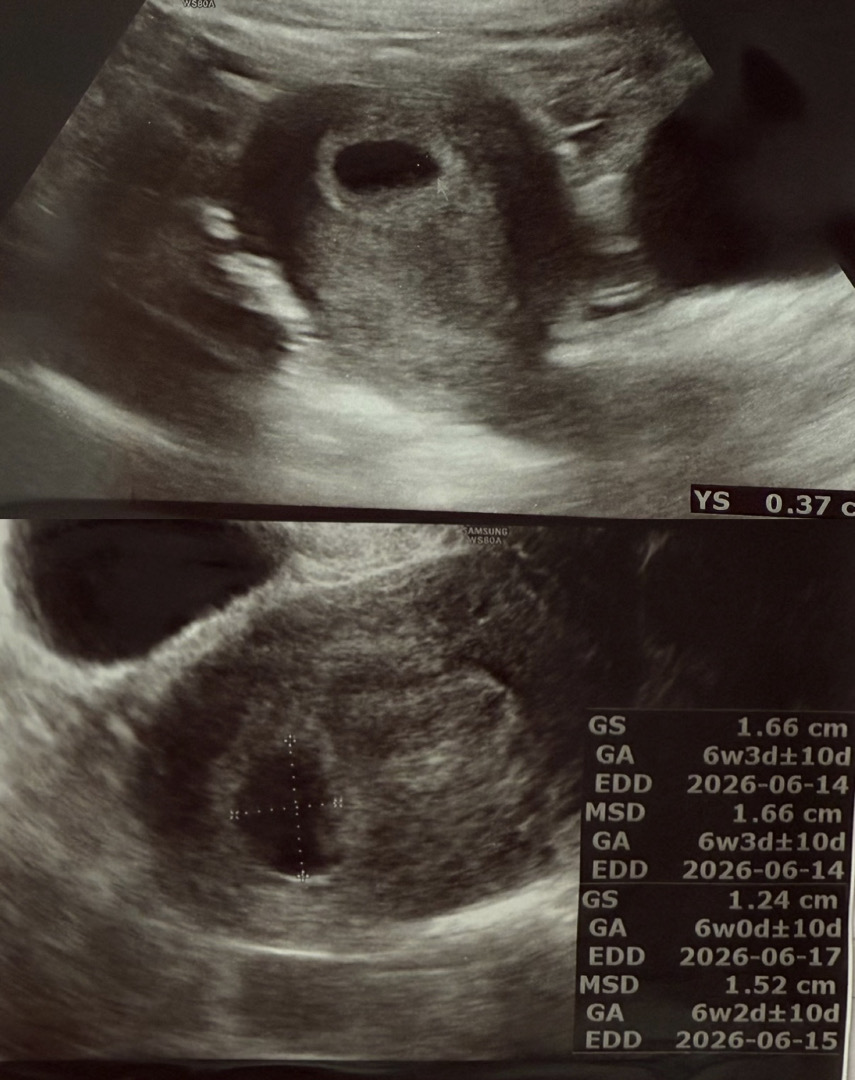

오늘 아기집과 난황 보고 왔어요.ᐟ

오늘 마지막 생리시작일 기준으로는 5주 6일차입니당.ᐟ 처음 진료 받고 아기집 볼때 얼마나 기분이 좋았는지.. 근데 또 난황이 선명하지 않은거같아서 걱정이 되는 어쩔수없는 초보임산부에요.ᐟ 선생님이 주수에 맞게 잘 크고 있고 아기집도 자리를 잘잡았으며, 난황도 보인다고 걱정 안하셔도 된다구 하셨는데 안심이되면서도 걱정이되는 ㅎㅎ 다들 초음파 보고 오시면서도 저처럼 걱정을 하셨나요~?ㅠㅠ 아.ᐟ 그리고 아래 사진보면 6주 2일 아니면 3일로 예상된다는게 맞을까요? 선생님께서 심장소리 들을려고 하면 들을 수 있겠지만 아직 아기는 확인되지 않으니 다음주에 보자고 하셨어요.ᐟ 이 주수에는 이게 맞나요~? 선생님은 초음파로 잘 보이는 산모가 있고 그 보다 조금 덜 보이는 산모도 있다구 하시던데 ㅠㅠㅠ 꾹 참고 초음파로 확인하고 와서 행복하면서도 걱정되는 초보맘입니다 ㅎㅎ